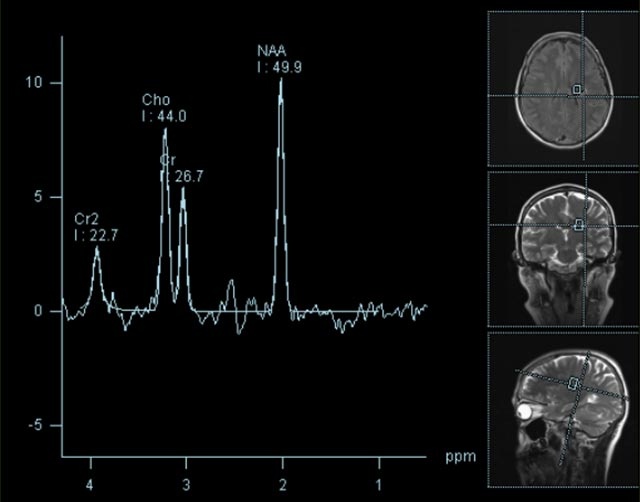

- Diffusionswichtung

- Perfusionswichtung

- Suszeptibilitätswichtung

- MR-Spektroskopie

Diese Verfahren werden bei verschiedenen Fragestellungen in verschiedenen Körperregionen in die Messprotokolle sinnvoll eingefügt. Teilweise können dadurch Differenzierungenverschiedener krankhafter Prozesse verbessert werden.